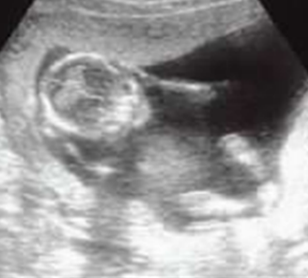

- 左:さんかくの顎

- 右:まるい顎

文字通り、お口の成長において「左側の成長が△」で「右側の成長が◯」です。乳歯列期のすきっ歯は、ほぼ問題ありません。そうでなければ、乳歯より大きな永久歯は並べません。

まるい顎とさんかくの顎

資料の左側のまぁるい顎が理想的に育った顎です。右側のV字のような三角形に近い形の顎は少々問題を抱えて成長している顎です。これは将来的に矯正治療が必要になる可能性を示すサインです。

一番上の抱っこの写真は、まるい顎やさんかくの顎に育つ過程の一例です。下の写真では「歯がきれいに揃いそう」や「歯並び悪くなりそう」は一目瞭然ですね。